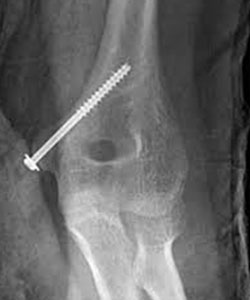

Image Courtesy - https://www.orthobullets.com/pediatrics/4008/medial-epicondylar-fractures--pediatric

Figure 3

Figure 3 shows the most common mechanism of fixation. An incision is made directly over the medial epicondyle and care is taken to identify and protect the ulnar nerve. The fracture is reduced and then a k-wire is placed to hold the reduction. A cannulated screw is then placed over the k-wire and then the k-wire is removed. There is very little soft tissue around the elbow which can lead to prominent hardware. This hardware can become bothersome for many patients and may require removal in the months following surgery once the fracture is healed.